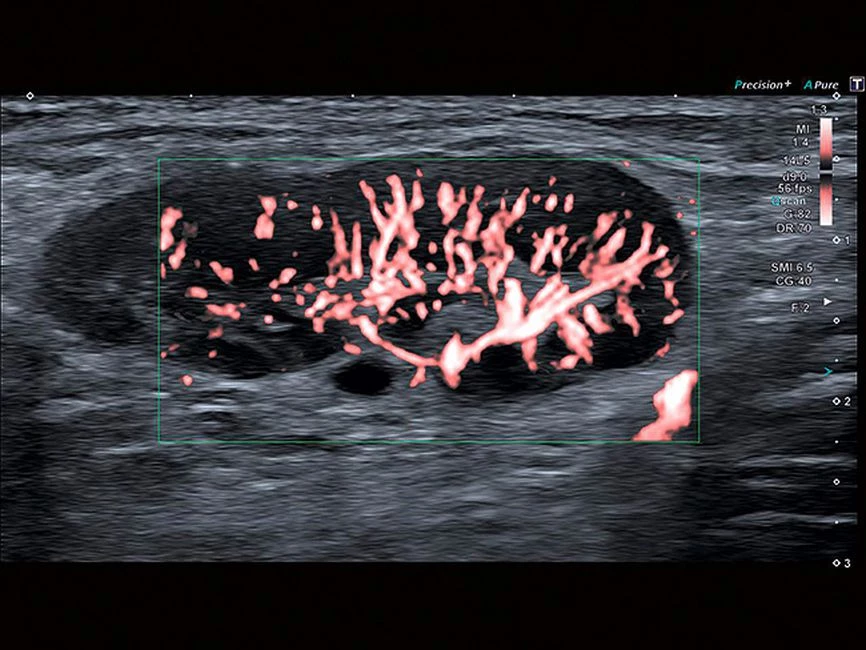

- SMI. Опция, упрощающая визуализацию микроциркуляторного русла. С ее помощью обследуются сосуды с низкой интенсивностью кровотока, изучаются наиболее тонкие структуры. SMI упрощает диагностику новообразований, минимизирует вероятность ошибки.

Уровень сосудистой визуализации SMI в сочетании с высокой частотой кадров повышает диагностическую достоверность при оценке поражений, кист и опухолей.

SMI с цветовой кодировкой позволяет одновременно отображать информацию о потоках и оттенках серого с высокой временной и пространственной информацией.